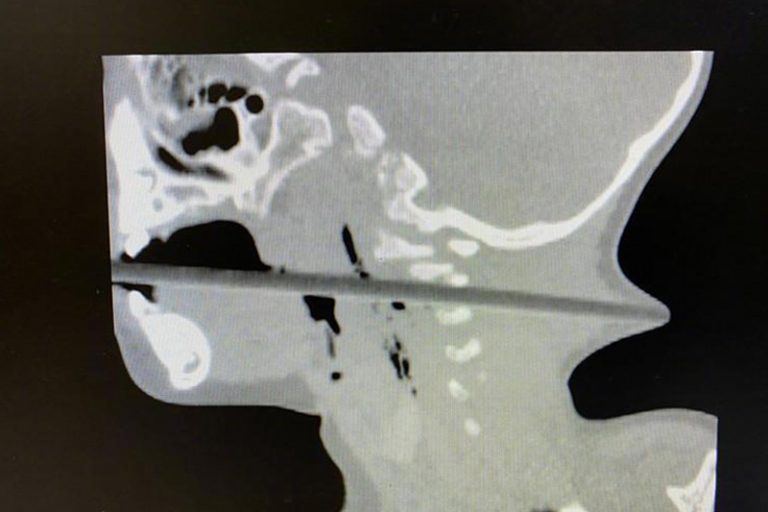

家人其後將林林送往南京市兒童醫院求診,該院神經外科主治醫師邱德智立即為林林安排做檢查。結果發現,長20多厘米的筷子從患者的「口腔進入,經過咽部後壁,通過頸椎2、3 間隙,一直向後到達後頸,幾乎戳穿了皮膚,從後頸可以清晰地看見筷頭。」

邱醫師續指,幸而筷子未有傷及林林的食道和氣管,但卻憂慮椎動脈和頸神經或已受損,在手術過程中有可能造成大出血,就會有生命危險。